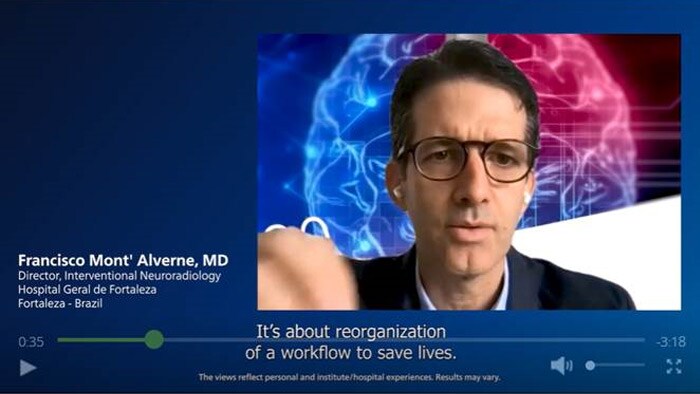

Experts explain how Direct to Angio Suite workflows shorten door to re-perfusion times for their ischemic stroke patients and how more patients can benefit from mechanical thrombectomy through changed guidelines.

An interview with (interventional) neurologists about the importance of the direct to angio approach, and the challenges they face.

Dr. Marc Ribó explains how Direct to Angio Suite workflows shorten door to re-perfusion times for their ischemic stroke patients.